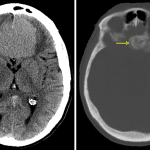

Age: 65

Sex: Female

Indication: Headache

Meningioma